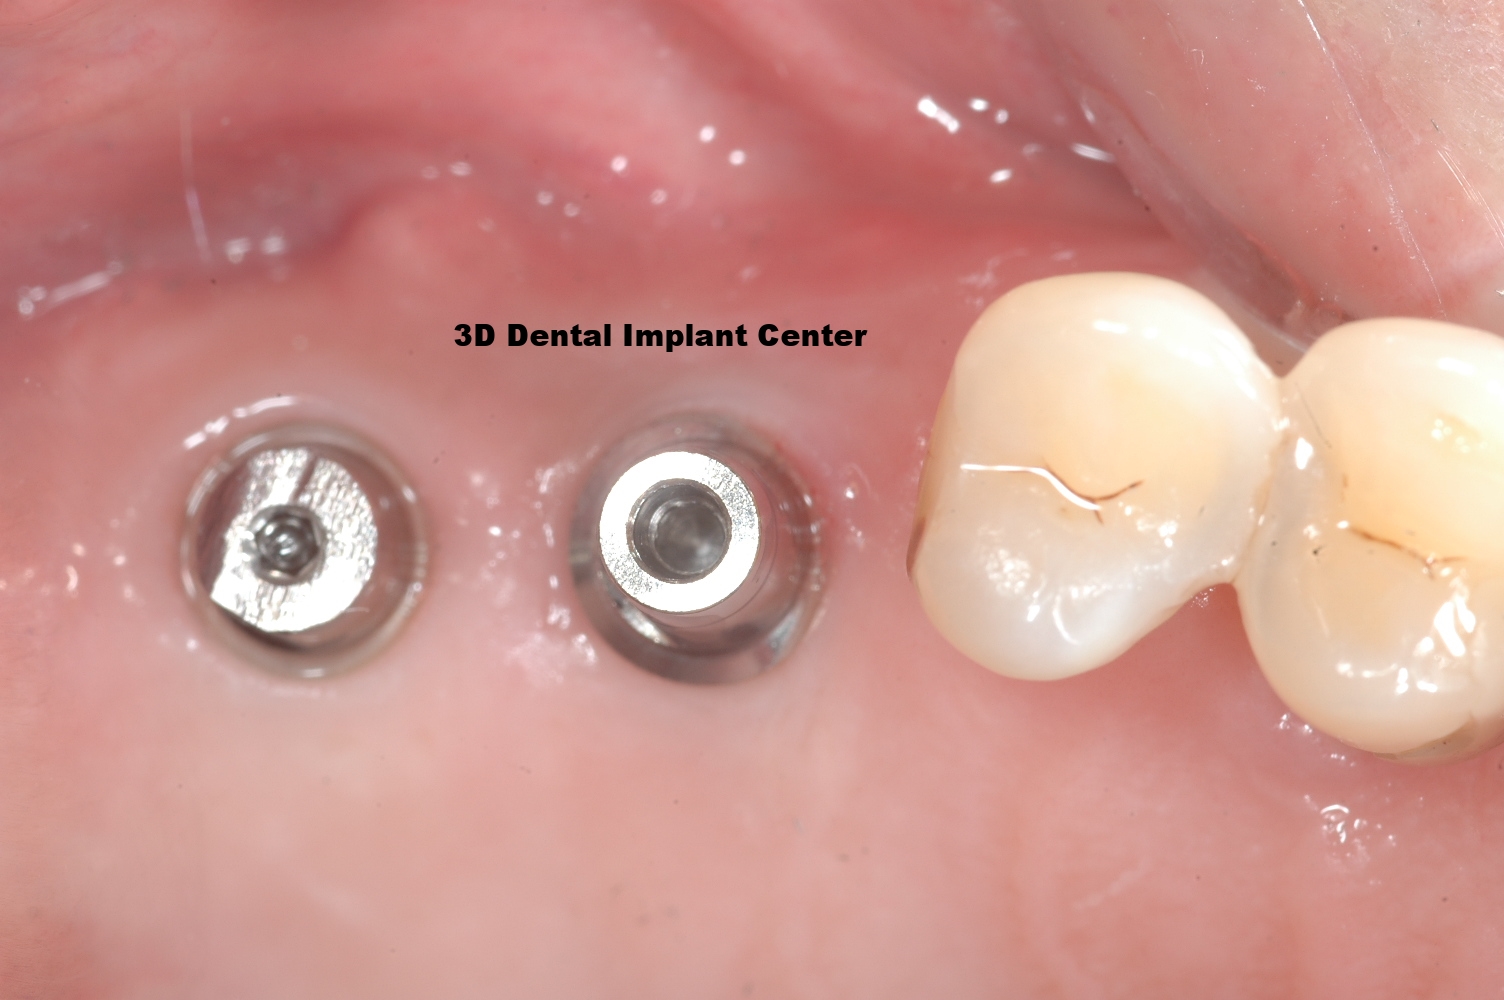

Case #4: This 60 year old male patient came in with severe periodontal disease. Note that he already had dental implants done in another office 1 year ago. You can see the dental implants on lower right side is getting bone loss.This 60 year old male patient came in with severe periodontal disease. Note that he already had dental implants done in another office 1 year ago. You can see the dental implants on lower right side is getting bone loss.

All upper implants has been placed in our office. Note that lower right implant (done in another office) continues to have bone loss. They will eventually fall out and would require extensive bone grafting. Patient are able to get more dental implants on lower right side if he's lucky and bone loss is not extenisve. If bone loss is extensive on failing implant, patient might not have enough bone for further dental implants in that area. This is an example it is very important to find a good, experienced and skilled clinician to do these procedures because sometimes you really only have 'one chance'.

Upper implant in temporary phase.

Note the amount of bone loss on the lower right implants that was done by another office. There can be many reasons that can lead to this type of failure, it takes an experienced clinician to avoid these type of issues. These failing implant would need to be removed and bone grafted, hopefully, new dental implants can be placed.